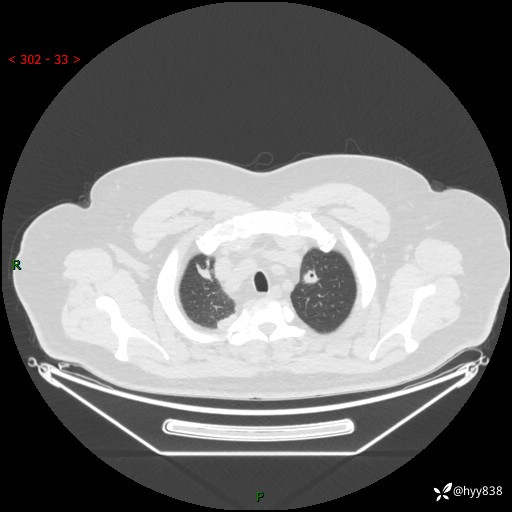

病例中年男性,发热来诊。典型?鉴别疾病谱有哪些,下一步---结果公布~

性别:男

年龄:48岁

简要病史:发热来诊(门诊病人)

胸部CT平扫